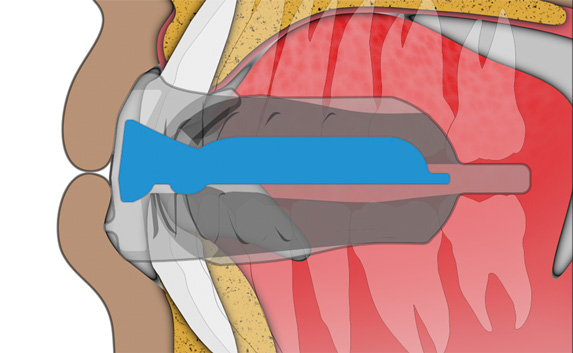

Tongue tag

encourages correct tip of the tongue positioning.

Tongue elevator

encourages the body of the tongue to rest in the roof of the mouth.